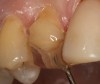

Magne23 described the technique of immediate dentin sealing with the use of a three-step dentin bonding adhesive system. The author has made modifications to this technique as follows. After the tooth has been prepared and isolated, the enamel and dentin are etched with 35% phosphoric acid for 30 and 15 seconds, respectively (Figure 1). Both surfaces are then thoroughly rinsed with water and gently air-dried for 5 seconds. A desensitizer is then vigorously applied to the dentin surface with a microbrush applicator for 30 seconds (Figure 2). To remove excess desensitizing agent from the dentin surface, the microbrush applicator is dried with a gauze pad and then brought back to the wet dentin surface to absorb the excess desensitizer. This step is repeated twice and provides a sufficient wet surface to the dentin. Next, a primer is applied to the enamel and dentin with a microbrush applicator using a light scrubbing motion for 30 seconds (Figure 3). Using light air pressure, the excess primer is air-thinned but still leaves a slightly moist surface. In other words, the surfaces are not desiccated but are left moist. An adhesive is then applied to the enamel and dentin surfaces using a scrubbing motion with a microbrush applicator (Figure 4). The adhesive should be left in contact with the tooth for 30 seconds and then air-thinned. A second coat of adhesive is then applied for the same length of time before it is air-thinned. The adhesive is then light-polymerized for 5 seconds. This step is necessary to fix the adhesive in place before applying a water-soluble glycerin gel. After the initial light polymerization, the gel is applied with a syringe over the adhesive-covered area to block out the oxygen (Figure 5). This step is necessary to eliminate the formation of an oxygen-inhibited layer on the adhesive surface. The presence of the oxygen-inhibited layer can interfere with the surface polymerization of polyvinyl and especially polyether impression material.24 The polymerization of the adhesive is then resumed (Figure 6) for 30 seconds. The glycerin gel is washed away and the tooth is air-dried. A scaling instrument is then used to remove any adhesive flash remaining beyond the margin. After the impression, the temporary restoration can be fabricated and placed with non-eugenol provisional cement.

Figure 4  An adhesive was then applied to the enamel and dentin surfaces using a scrubbing motion with a microbrush applicator.

Figure 4